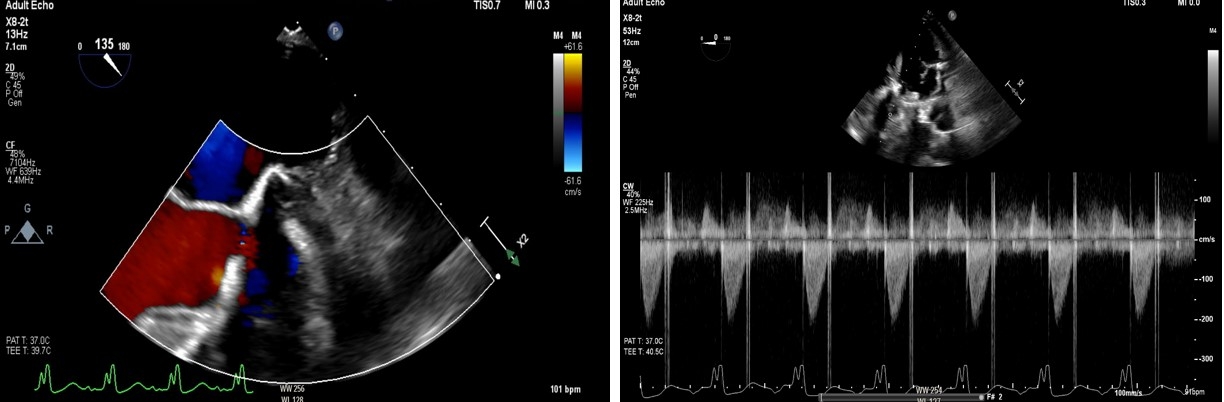

Transthoracic echocardiography (TTE) revealed a peak gradient of 3.7 m/s and mean gradient of 28 mmHg across the prosthetic valve. Urgent transesophageal echocardiography (TEE) showed severely restricted leaflet motion with torrential aortic regurgitation—highly suggestive of valve thrombosis. Due to prohibitive surgical risk, thrombolysis with alteplase (25 mg over 6 hours) was administered. Repeat TEE demonstrated improved leaflet motion (velocity 2.2 m/s, mean gradient 17.6 mmHg), LVEF of 25%, and new severe mitral regurgitation. He was stabilized on milrinone and extubated by hospital day five.